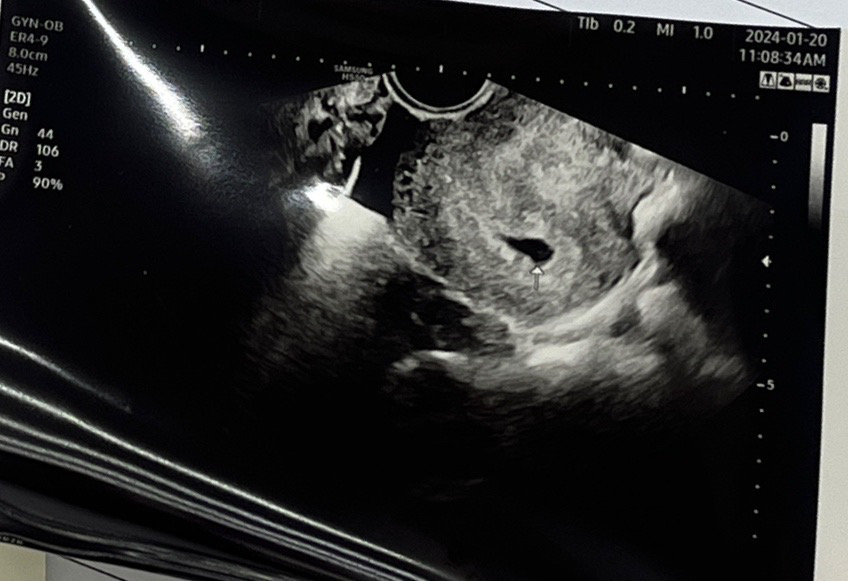

어플상 5주6일 초음파 보고왔는데요ㅠ

주기가31일이라 조금 늦은?거 같다고 하시고, 아기집만 저렇게 있네용 ㅠㅠ 괜찮은거 맞겠죠?? 모양이 다들 동그랗고 예쁘던데 이상한 모양인거 같구ㅜㅜㅜ 2주 뒤에 다시 보자는데 맘이 계속 불안하네요 ㅜㅜ